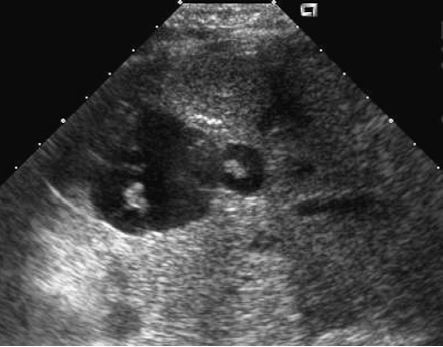

Caroli’s disease

• central dot sign = cystic lesions with central solid components containing blood flow

• complications

• biliary stones

• bild duct obstruction

• cholangitis

• liver abscess

• hepatic fibrosis –> portal hypertension

• cholangiocarcinoma

• the kidneys may also be affected with a variety of cystic diseases